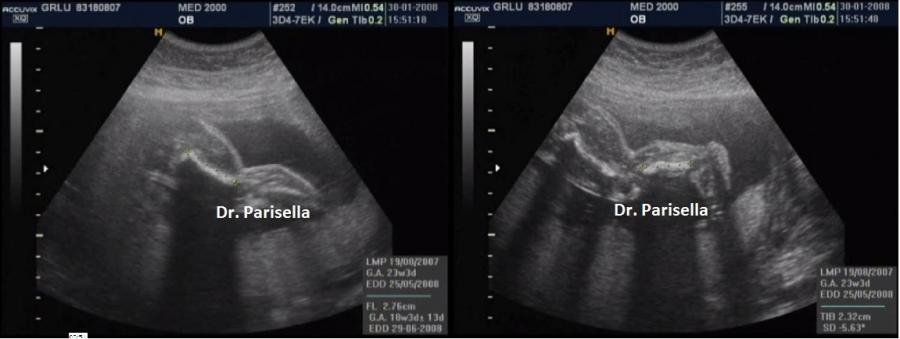

E' una rara collagenopatia a trasmissione autosomica dominante causata da mutazioni del gene COL2A1, che codifica per il collagene tipo 2, caratterizzata da accorciamento rizomelico delle ossa lunghe e ipoplasia mediofacciale (viso tondo e radice del naso piatta); comune è la palatoschisi e occasionalmente l'associazione con la sequenza di Pierre Robin e quindi la presenza di micrognazia. Spesso vi è anche interessamento della colonna vertebrale con platispondilia e schisi coronali.  Segni radiografici sono l'assenza della testa del femore, l'ingrandimento della metafisi prossimale del femore, le epifisi ingrandite.

La diagnosi precoce è impossibile in quanto la biometria delle ossa lunghe diviene anormale solo nel III trimestre di gravidanza.